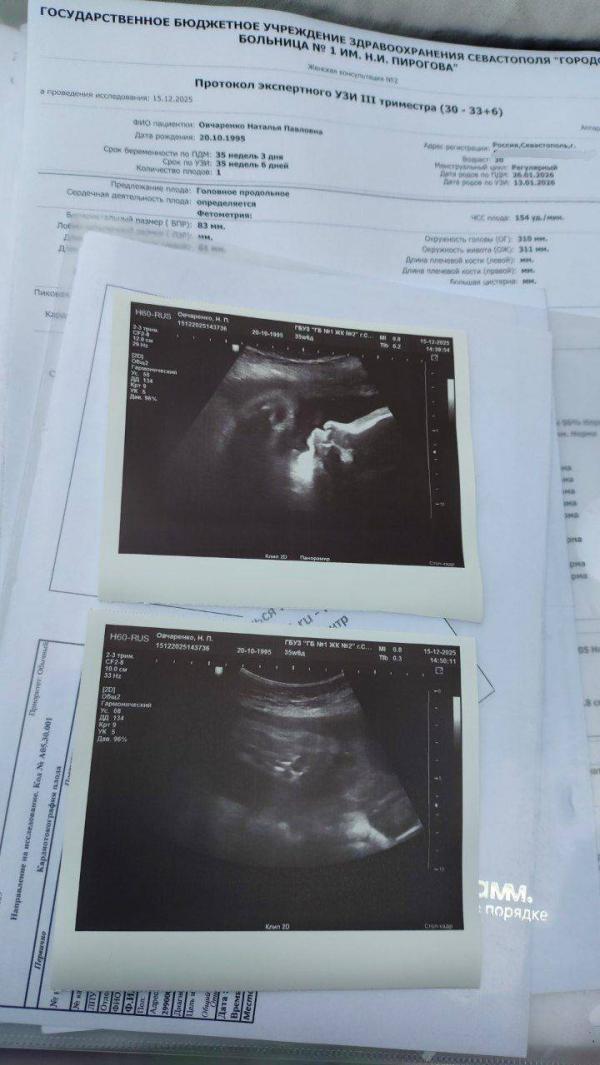

А мы вчера ездили на УЗИ! Третий скрининг!)🥰

Показали мне мою девочку вдоль и поперек!) Сказали что у меня очень красивый человек растет, обвитие малышка сняла, по всем данным шикарная беременость и показатели максимальные, что на УЗИ что на КТГ!)